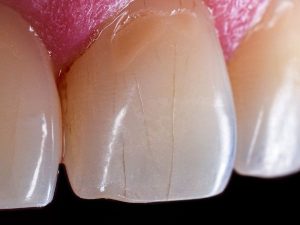

Cómo eliminar las manchas dentales y recuperar el color natural

Las manchas dentales pueden ser una fuente de preocupación para muchas personas, ya que afectan no solo...